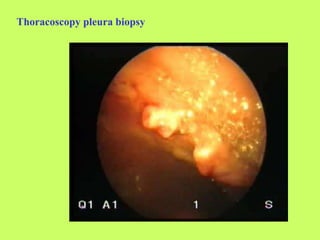

6. Thoracoscopy with biopsy of pleura.

Thoracoscopy: pleural adhesions, biopsy.

Thoracoscopy pleura biopsy

Mesothelioma: thoracoscopy picture – bumpy surface,

hemorrhagic exudation, adhesions.